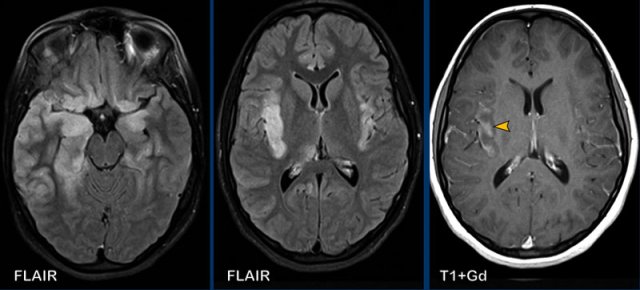

These images are of a 55-year old immunocompromised patient, who presented with cognitive complaints and headache.

Images

FLAIR shows non-supressed enhancing CSF in the subarachnoid

space.

Look along the cerebellar foliae, these are hyperintense on FLAIR (black arrowheads).

There is faint leptomeningeal enhancement (yellow arrowhead).

Furthermore there is high FLAIR signal at the

perivascular spaces in the semioval centre with enhancement.

Conclusion

This turned

out to be cryptococcal meningitis.

The spread

along the perivascular spaces in an immunocompromised patient is suggestive.

Sometimes in these patients there are also pseudocysts.